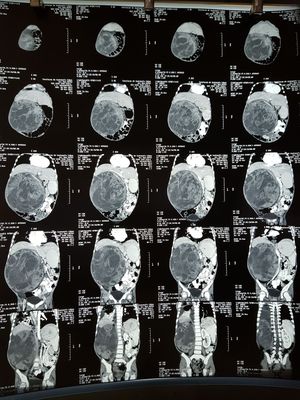

Kidney

Tumor